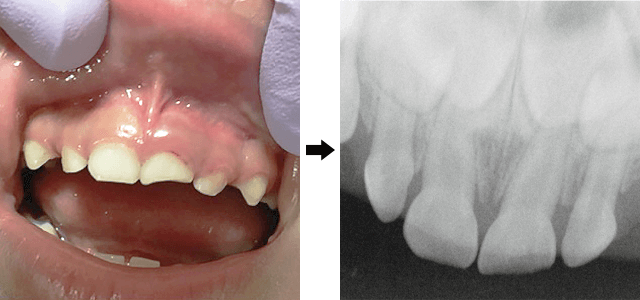

▲欠けてますが、

レントゲンで神経まで折れてないことが

確認されたケース

▲乳歯の根っこに、水平に割れ目が見られる様子

上の写真を見てください。

骨の中で歯の頭だけができてるのが、生える準備をしてる永久歯です。乳歯とは、全くつながっていません!!

▲乳歯の神経が腐って膿んでる様子

この場合、どんな影響が出るかというと、膿のせいで永久歯が黒ずんで生えてしまったり、膿をよけて永久歯が生えようとするので、永久歯の生える位置がずれてしまって、歯並びが悪くなる可能性が高くなります。